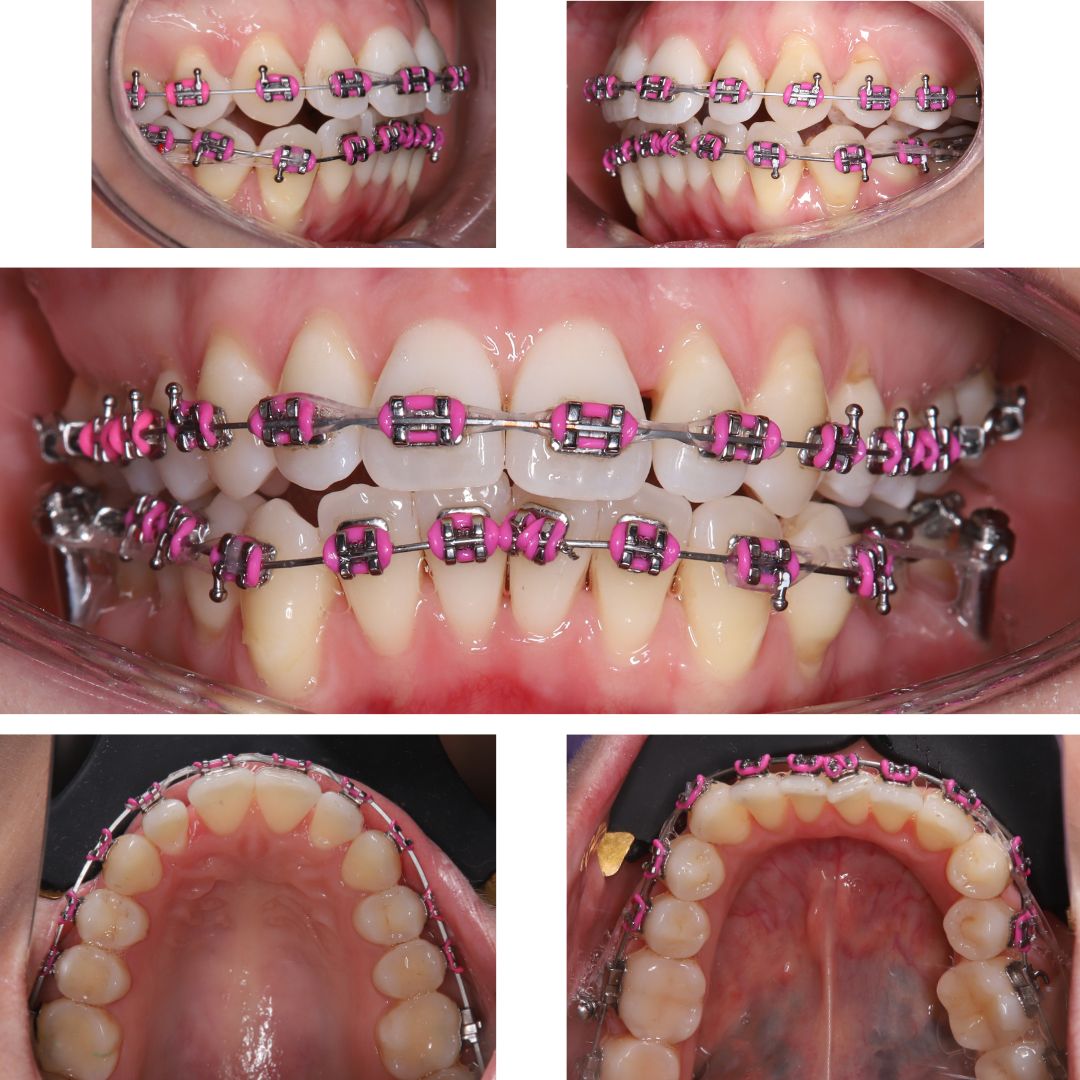

МЫ СМОГЛИ ДОБИТЬСЯ РЕЗУЛЬТАТА ПРОВЕДЯ ДИСТАЛИЗАЦИЮ – смещение жевательных зубов на верхней и нижней челюсти назад. Такое лечение проводится с установкой миниимпланататов, которые служат опорой для крепления тяги идущей к зубу или группе зубов, которые нужно сместить.

Примечание: ортодонтические миниимплантаты не срастаются с костью и удаляются после завершения лечения.